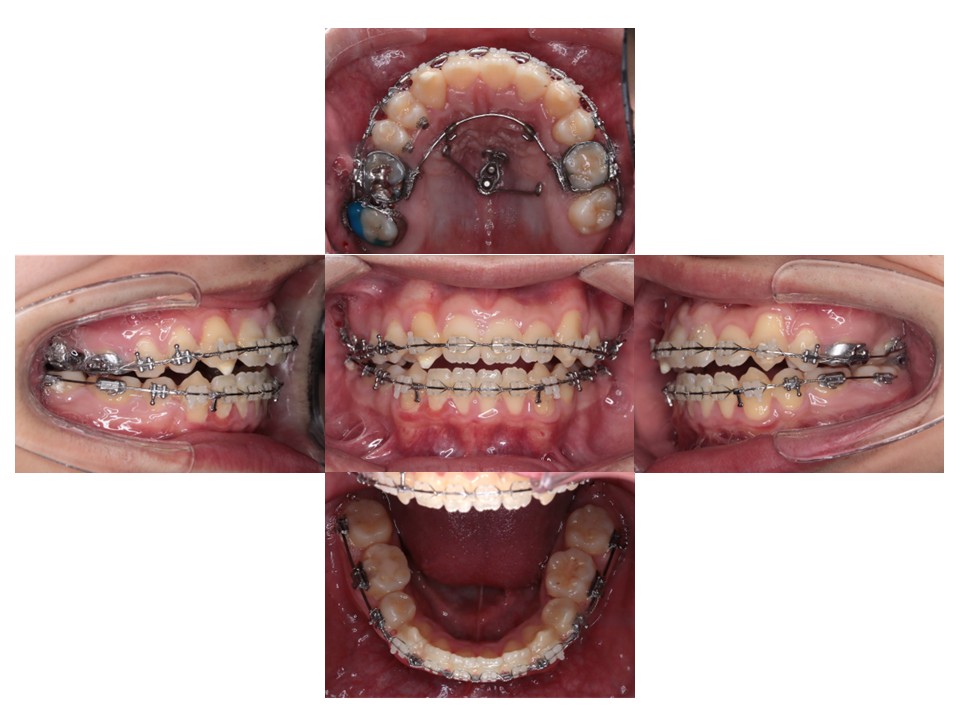

手術直前